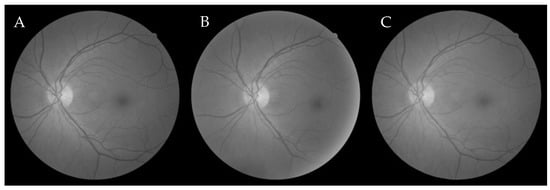

6.2.2. Firefly Algorithm-Based Wang’s Demons Registration